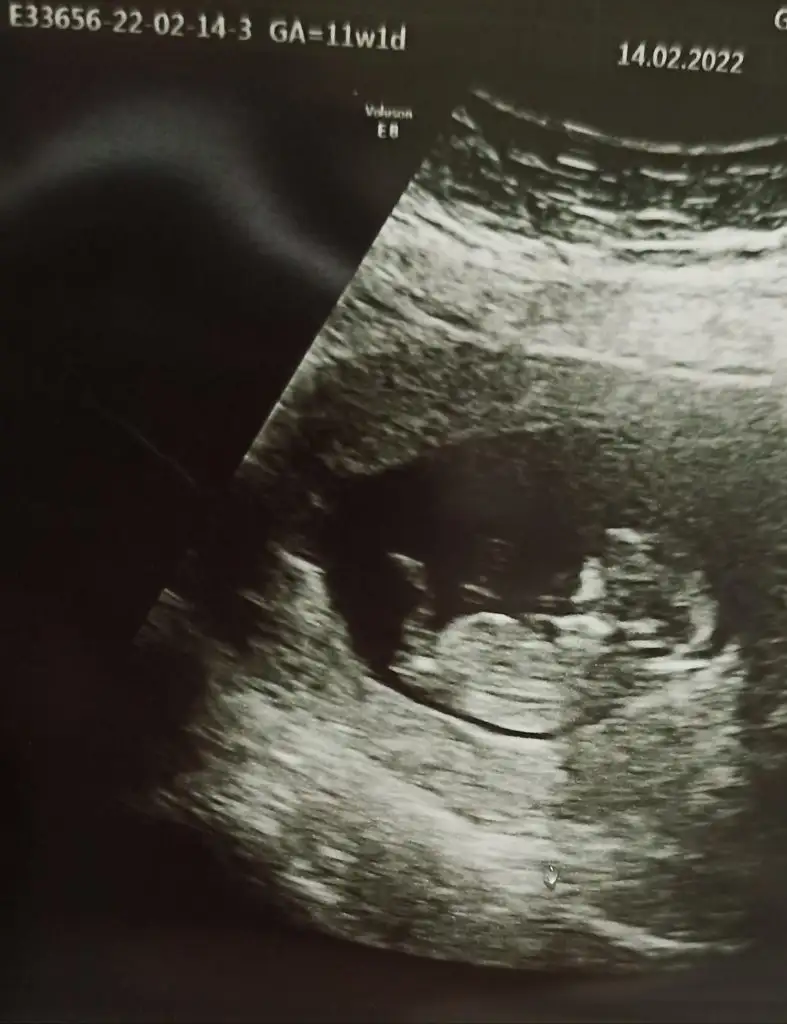

Beni de yine atladınız sanırım...Ikra meyra Tam 13 haftalığz doktor bır tahminde bulundu ama degısır mı bılemedım bize de bır bakabilir mısınız

Eki Görüntüle 3003879